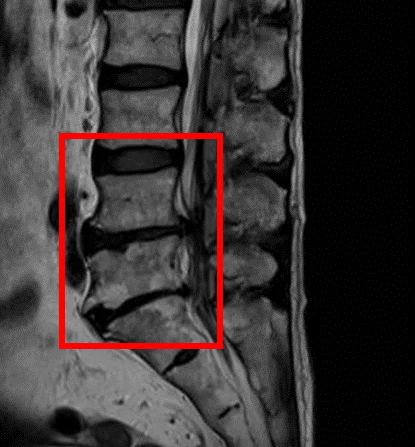

По данным МРТ и результатам осмотра пациентки выявлена дегенерация межпозвоночных дисков L3/L4, L4/L5, L5/S1, а также стеноз позвоночного канала на уровне дисков L4/L5 и L5/S1.